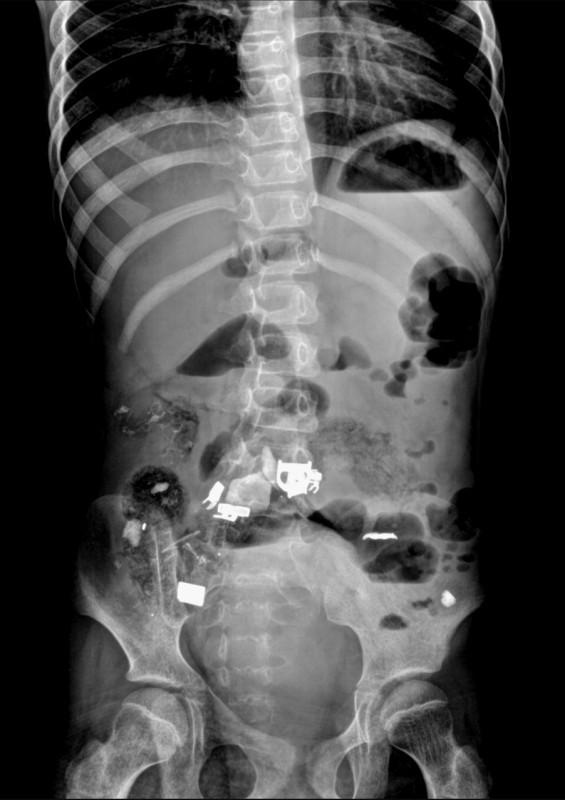

Ребенка, который страдает ДЦП и задержкой психического развития, экстренно госпитализировали с жалобами на боли в животе и рвоту. Врачи провели всестороннее обследование организма, рентген показал инородные предметы в брюшной полости. Инцидент произошел в феврале, но известно о нем стало только сейчас.

"Благодаря оперативному вмешательству врачей, в ходе операции в кишечнике девочки благополучно обнаружены и вытащены инородные тела - железо, ручка, скотч, волосы", - сообщили в пресс-службе областного управления здравоохранения.